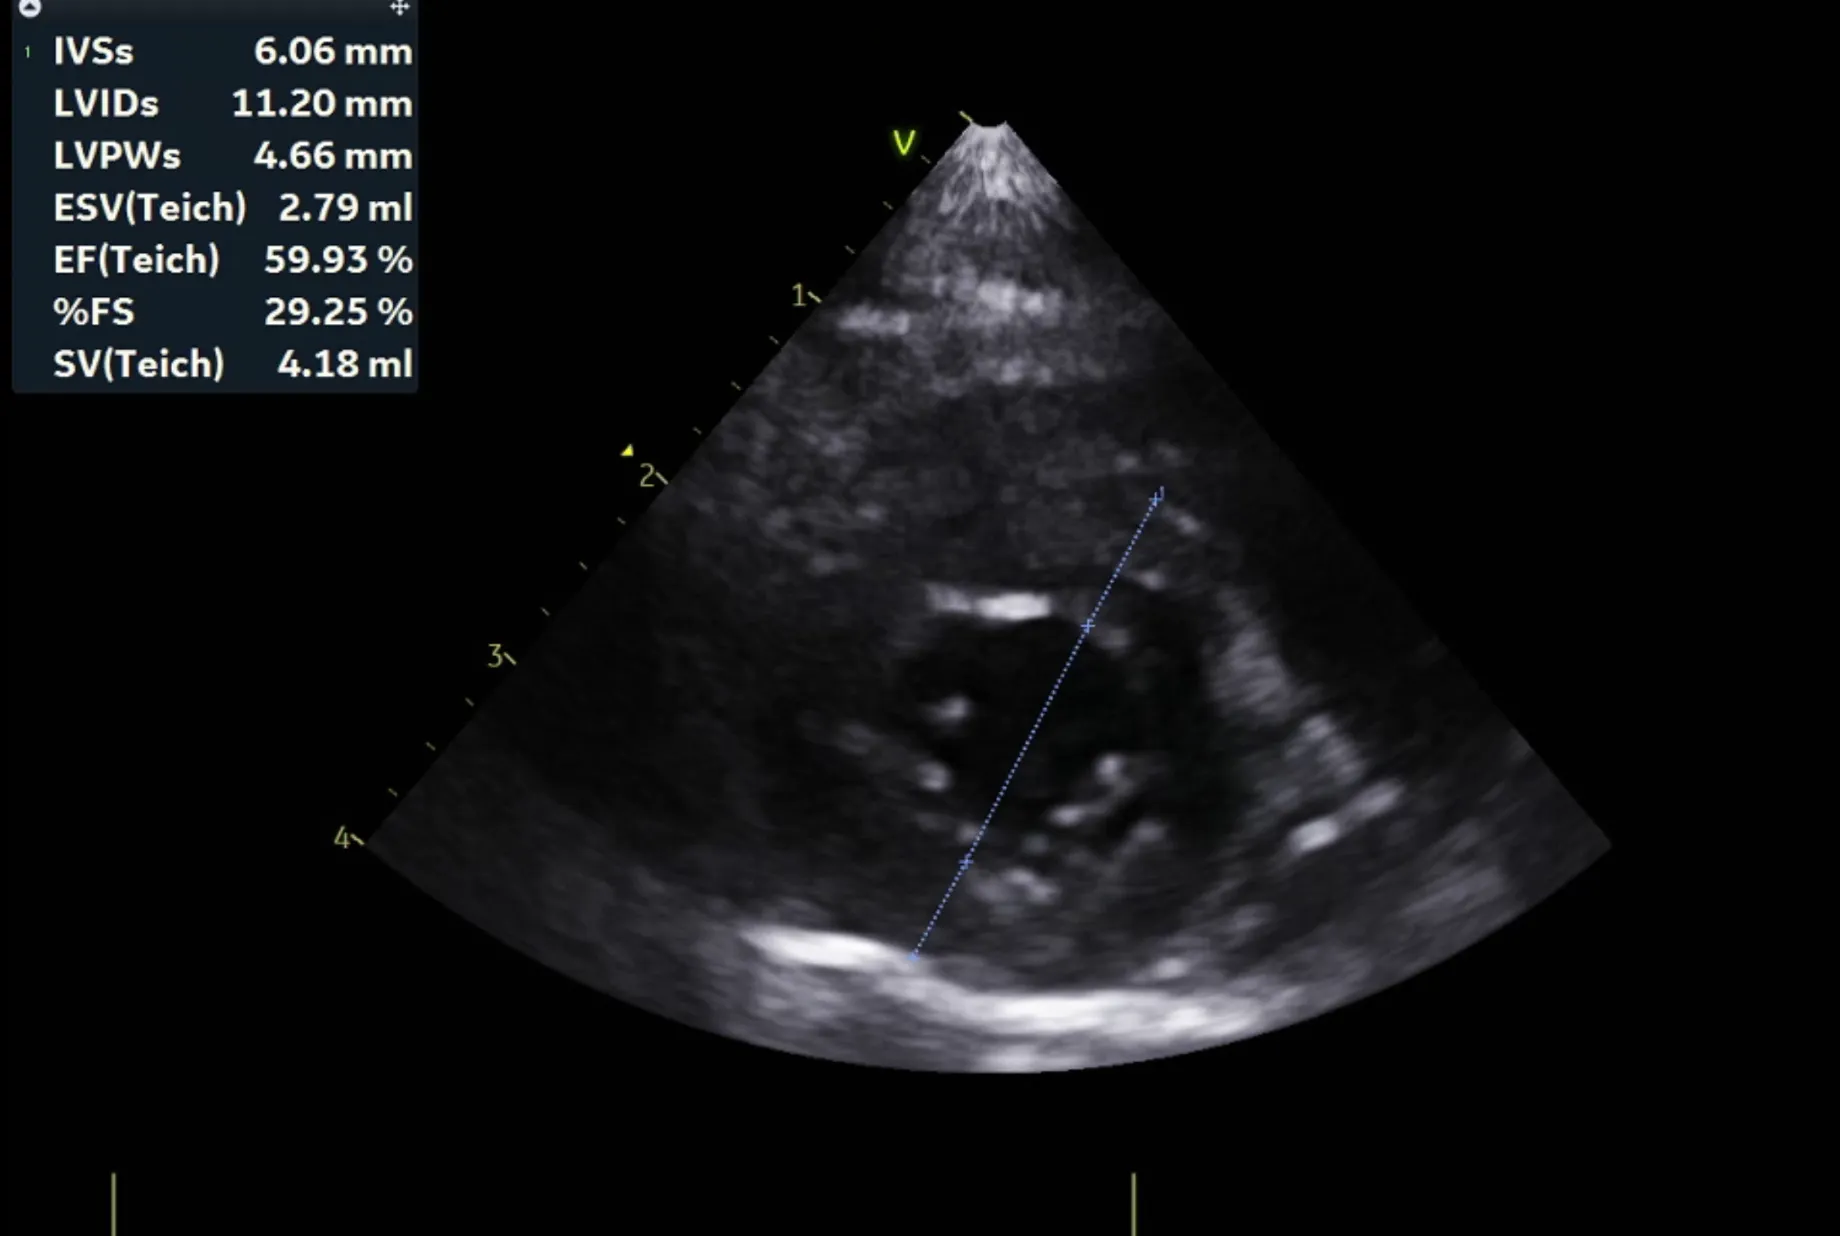

분류 수치

IVSd 4.66/4.58(2.80 - 4.90㎜) - 정상/정상

LVIDd 15.83/15.17(12.20 - 19.20㎜) - 정상/정상

LVPWd 4.21/4.09(2.80 - 4.80㎜) - 정상/정상

IVSs 6.06/5.17(4.30 - 8.40㎜) - 정상/정상

LVIDs 11.20/10.69(5.50 - 12.60㎜) - 정상/정상

LVPWs 4.66/5.02(4.60 - 8.50㎜) - 정상/정상

EF 59.9%/60.5%(40% - 67%) - 정상/정상

FS 29.3%/29.5%(30% - 49%) - 감소/감소

LVIDDN 0.98

EDVI 23(~100)

ESVI 9(~30)

Echo_comments

HCM으로 의심될만한 소견 관찰되지 않음

주치의 소견은 다음과 같습니다.

곰이 는 심장 초음파 검사 결과 현재 심잠벽의 두께는 정상이며 수축기능, 이완기능(심장이 정상적으로 잘 뛰는 것을 확인하는 검사) 모두 정상입니다.

심장 초음파는 1년에 한번씩 검사 받는 것을 추천드립니다.